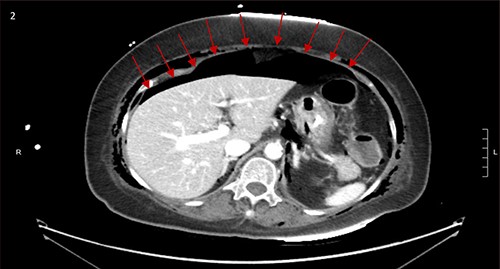

CT scan showed small bilateral pneumothoraces (Fig. 1a) in the setting of several mildly displaced anterior rib fractures with associated subcutaneous emphysema (Fig. 1b), as well as extensive intraperitoneal (Fig. 2), extraperitoneal and retroperitoneal (Fig. 3) air. However, imaging was negative for evidence of perforation. Given concern for abdominal compartment syndrome as evidenced by abdominal distension on exam, initially elevated peak pressures to 24 immediately following intubation, and CT findings of pneumoperitonum, the General Surgery service was consulted for evaluation and further assistance with management. On clinical exam, the patient’s abdomen was distended without tenderness, guarding, or rebound. Laboratory results were notable for white blood cell count of 21.1 per mm3, platelet count of 314 per mm3, and a whole blood lactate of 8.1 mmol/l. Her leukocytosis, though only mildly increased from her baseline of 15 over the previous days, was attributed to known Staphylococcus bacteremia for which she was on antibiotic therapy with a contribution from her shock and PEA arrest. Given the patient was hemodynamically stable with no signs of an acute abdomen, we decided to manage with serial abdominal exams without operative intervention. The patient was closely followed over the subsequent 5 days, during which time she remained stable; she no longer required pressors and was weaned to trach collar on post-arrest Day 2; her white blood cell count continued to downtrend and normalized post-arrest Day 7 as she remained on antibiotic therapy; no additional abdominal imaging was obtained, given her very benign abdominal exam. Operative management was never utilized and she remained asymptomatic. While in the intensive care unit, the patient improved and she was able to engage in physical and occupational therapy despite the pneumothoraces. She was discharged to a long-term acute care hospital on hospital Day 36.

Bilateral retroperitoneal air surrounding right and left kidneys.